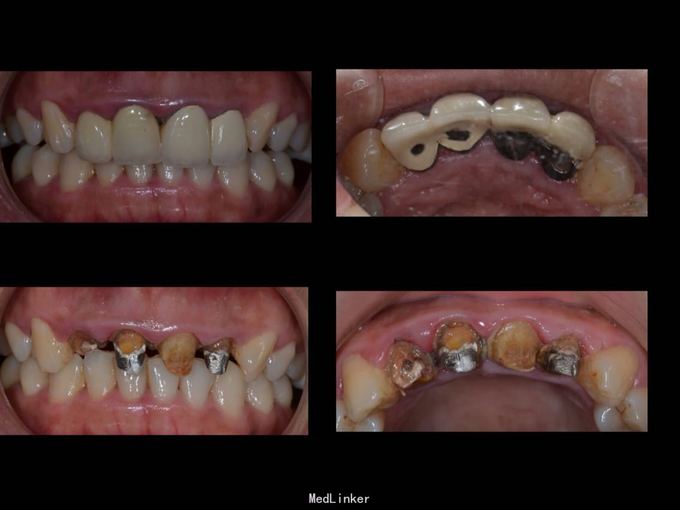

上门牙外伤金属烤瓷冠修复七年,牙龈发黑,红肿,有异味,颜色黄不美观,其他牙也黄不美观,要求重新修复

11 12 21 22金属烤瓷冠修复,牙龈发黑,冠颈部牙龈萎缩红肿有黑褐色腐质物,探出血,叩(-).23近中颊侧扭转倾斜.36 37 46 47残根,松动轻,全口牙结石中度,牙齿颜色偏黄,全景片示,11 12 21 22根管治疗不完善,根尖低密度影,有金属桩修复

11 12 21 22死髓牙,不良修复体,牙龈炎 36 37 46 47残根 牙列不齐 处置:全口洁治。 比色,拍照,取模型做蜡型。 拆除旧修复体,拆桩核,做根管治疗,纤维桩修复,牙体预备,取模,做临时冠,粘固。11 12 21 22全瓷冠修复,13 14 23 24 31 32 33 34 41 42 43 44瓷贴面修复。

1.旧修复体覆合大,11 212 21 22龈缘位置较低且不对称,能做冠延长协调红白美学,更好 2.拆旧桩核要小心根折,用超声振动,一点一点拆.11桩核粘固比较牢固,根尖炎,定期观察行根尖手术倒充填。 3贴面的粘接,耐心